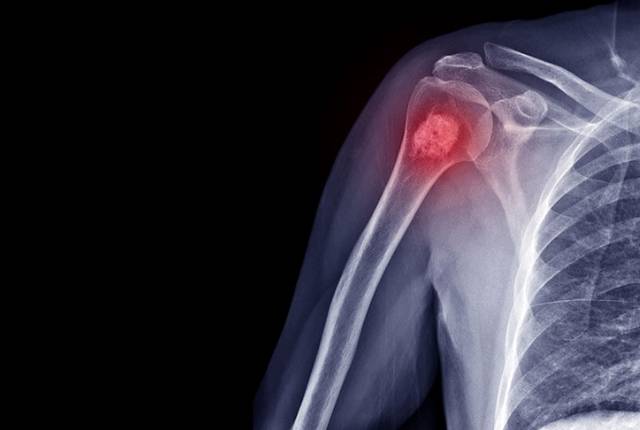

Comment diagnostiquer un cancer des os ?

Pour diagnostiquer un cancer des os, l’examen de référence est l’imagerie médicale, complétée par une biopsie. En fonction du type de cancer des os, les examens varient :

Ostéosarcome : radiographie thoracique, TDM, scintigraphie osseuse, IRM (Imagerie par Résonance Magnétique), TEP (tomographie par émission de positons) et biopsie.

Chondrosarcome : radiographie, scintigraphie osseuse, IRM et biopsie.

Sarcome d’Ewing ou lymphome osseux : radiographie, IRM, biopsie.

Myélome : s’il est isolé, IRM et TEP sont pratiquées. S’il est étendu, tout le corps est radiographié, des analyses de sang et une ponction de moelle osseuse sont effectuées.

Sarcome osseux indifférencié pléomorphe ou adamantinome : radiographie, biopsie.

Tumeurs malignes à cellules géantes ou chordome : IRM, biopsie.